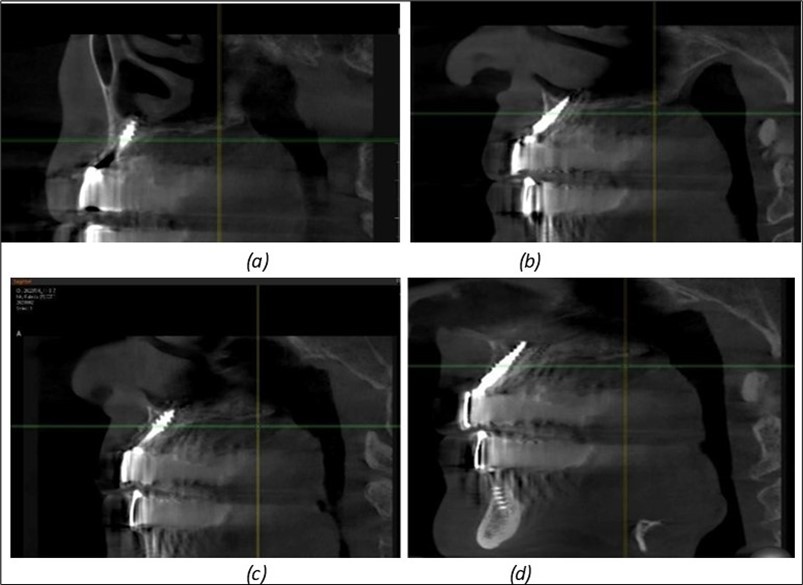

Figure 11.Implants in the anterior area anchored in the nasal cortex (BCS and TPG): (a), (c) – BCS implants fixed in the nasal cortex; (b), (d) – TPG implants fixed in the second nasal cortex with compression in the trabecular area.

Figure 12.Implants fixed distally in quadrant 4 with fixation at the level of the mylohyoid line: (a) The most distal implant fixed in unaffected bone from the previous restoration; (b) The implant fixed in the area where the two stage implant was removed.